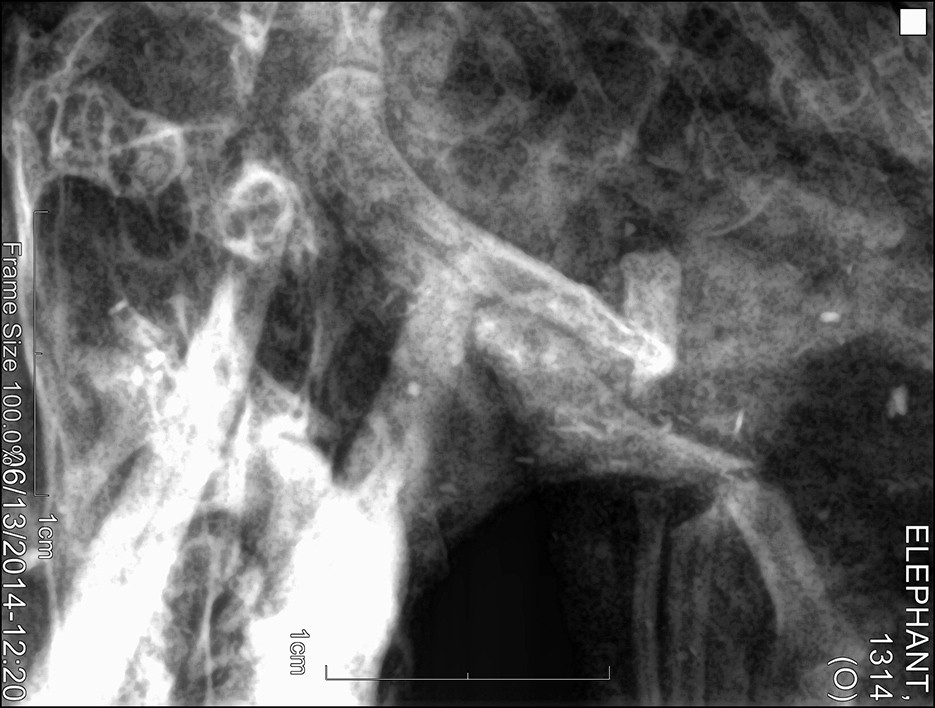

Der von ihm geforderte Beweis scheint inzwischen zumindest teilweise erbracht zu sein. Wissenschaftler und Forscher des Pha Woh Hospitals im Mae Sot Distrikt haben Überreste solcher Wasserelefanten untersucht. Die Röntgenaufnahmen der kleinen Körper zeigen, daß diese winzigen Wesen eine Knochenstruktur haben, welche jener der ausgewachsenen asiatischen Elefanten gleicht.

Röntgen1 Röntgen2 Röntgen3

(Original-Röntgenaufnahmen des untersuchten Exemplars)